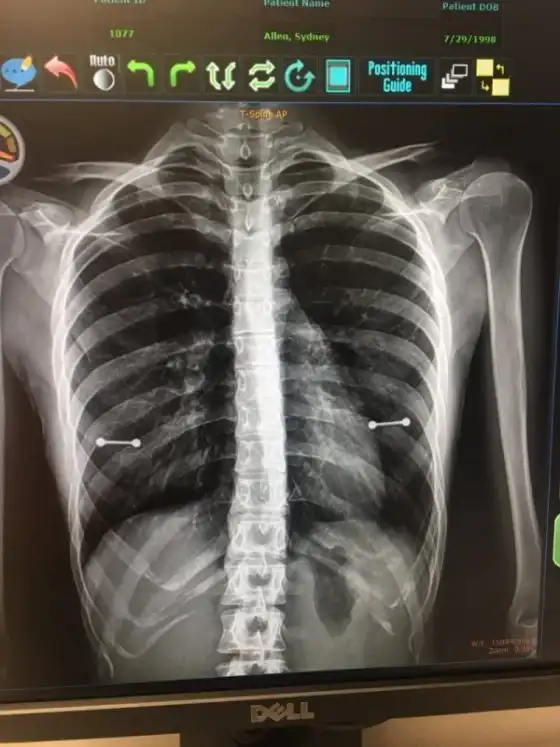

Врачи диагностировали у девушки искривление позвоночника, поэтому ей нужно было сделать рентген. Девушка зашла на рентген, медики сделали снимок, а мама как раз сидела в комнате ожидания. Когда снимок был готов, доктор показал матери, которая сразу же обратила свое внимание на странные металлические "болтики" в районе сосков.

Конечно же, сначала мать была в ярости, но затем сказала, что не стоило скрывать от нее такие подробности и в конечном итоге разрешила оставить сережки.